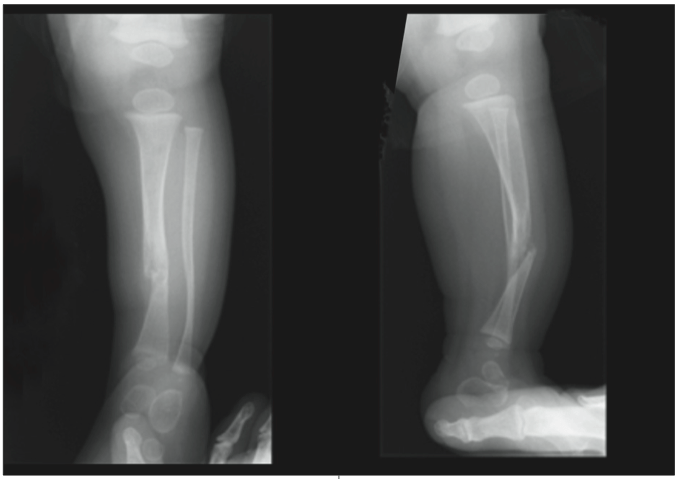

Врожденные заболевания: В редких случаях псевдоартроз может быть врожденным заболеванием. Например, у человека может быть врожденный псевдоартроз ключицы. Также возможен врожденный псевдоартроз большеберцовой кости.

Врачи назначают визуализирующие методы диагностики, такие как рентгенография или компьютерная томография, чтобы проверить наличие псевдоартроза. Данные методики дают подробную картину скелета, на основании которой можно поставить диагноз.

Авторы исследования 2021 года также рекомендуют хирургическое вмешательство для лечения врожденного псевдоартроза ключицы. Это включает в себя резекцию ключицы с использованием костного трансплантата из гребня подвздошной кости малого таза. Врожденный псевдоартроз большеберцовой кости может быть сложным в лечении. В исследовании, проведенном в 2021 году, говорится, что в среднем только 50% хирургических вмешательств по поводу данного состояния приводили к восстановлению без рефрактерности.

Однако хирургический метод, известный как намеренное перекрестное соединение большеберцовой и малоберцовой костей, увеличил вероятность успеха до 100% восстановления без рефракции.